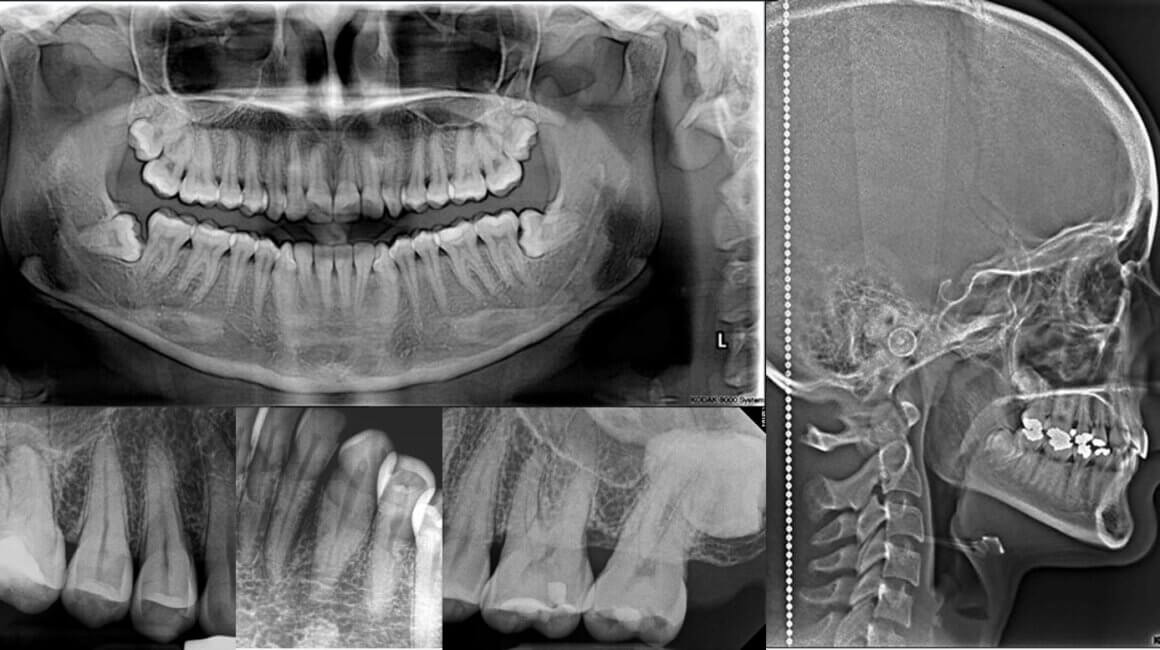

ORTOPANTOMOGRAFÍA O RADIOGRAFÍA PANORÁMICA

La ortopantomografía es una técnica extrabucal que se utiliza para examinar las maxilares superior e inferior en una sola placa. Frecuentemente se utiliza para complementar la información obtenida en las radiografís periapicales y de aleta de mordida.

Entre sus principales indicaciones se encuentran:

- Evaluar dientes incluidos, retenidos e impactados.

- Evaluar patrones de erupción, crecimiento y desarrollo dentario.

- Evaluación general del estado periodontal.

- Detectar manifestaciones de enfermedades sistémicas.

- Evaluación de lesiones extensas.

- Evaluación de fracturas en los maxilares.

- Evaluación de la apófisis coronoides

Ventajas:

Nos permite observar en una sola radiografia todos los dientes, los maxilares superior e inferior, la articulación temporomandibular, senos paranasales, fosas nasales, entre otras estructuras importantes. La técnica es relativamente sencilla. La dosis de radiación es relativamente baja, en especial en los equipos digitales.

RADIOGRAFÍA LATERAL DE CRÁNEO

(CEFALOMETRÍA LATERAL)

Esta radiografía sirve para evaluar el crecimiento y desarrollo facial, traumatismos y enfermedades, asà como anomalías del desarrollo; muestra los huesos de la cara y el cráneo junto con el perfil de tejidos blandos de la cara. Una de sus principales cualidades es que las radiograféas resultantes son comparables. Se pueden realizar trazados cefalométricos en ellas para evaluar las estructuras esqueléticas, dentarias y tejidos blandos. Es especialmente útil en dos campos fundamentales: ortodoncia y cirugía ortognética.

RADIOGRAFÍA DE ATM LATERAL BOCA ABIERTA Y CERRADA O COMPARATIVA DE ATM

Esta radiografía sirve para evaluar la articulación temporomandibular desde una vista lateral

Entre sus principales indicaciones se encuentran:

- Evaluar cambios de los componentes óseos articulares

- Detección de patologías articulares

- Evaluación del espacio articular

- Evaluación de la trayectoria condilar

Ventajas:

La ventaja principal es que es una radiografía que se enfoca en la ATM, en la cual se puede observar la estructura ósea tanto del cóndilo mandibular como de la cavidad glenoidea.

RADIOGRAFÍA PERIAPICAL O RETROALVEOLAR

Esta radiografía nos sirve para observar con detalle los órganos dentarios, el ligamento periodontal y el tejido oseo circundante a la raíces.

En sus principales indicaciones se encuentran:

- Detección de caries dental

- Evaluación del estado periodontal

- Evaluación del traumatismo dentoalveolar

- Evaluación de patología periapical y otras lesiones que afecten el hueso alveolar

- Evaluación de la presencia y posición de un diente no erupcionado

- Evaluación para cirugías menores y tratamientos endodónticos

Ventajas:

Esta radiografía tiene la ventaja de mostrar una zona dentaria con alta precisión, siendo de mucha utilidad para ver la anatomía dentaria completa, para evaluar la presencia de fracturas o lesiones cariosas, así mismo, se puede evaluar el tejido oseo de oporte y los cambio en el espacio periodontal. Por su tamaño pequeño la hace bastante precisa para evaluar un región de interés tanto en el maxilar superior como en la mandíbula.

RADIOGRAFÍA INTERPROXIMAL

(ALETA DE MORDIDA)

Esta radiografía se utiliza para examinar las superficies interproximales de los dientes, incluidas coronas de dientes superiores e inferiores, áreas interproximales y del hueso de la cresta alveolar. Con la finalidad de detectar caries interproximales, evaluar adaptación de restauraciones y valorar el estado de la cresta ósea.